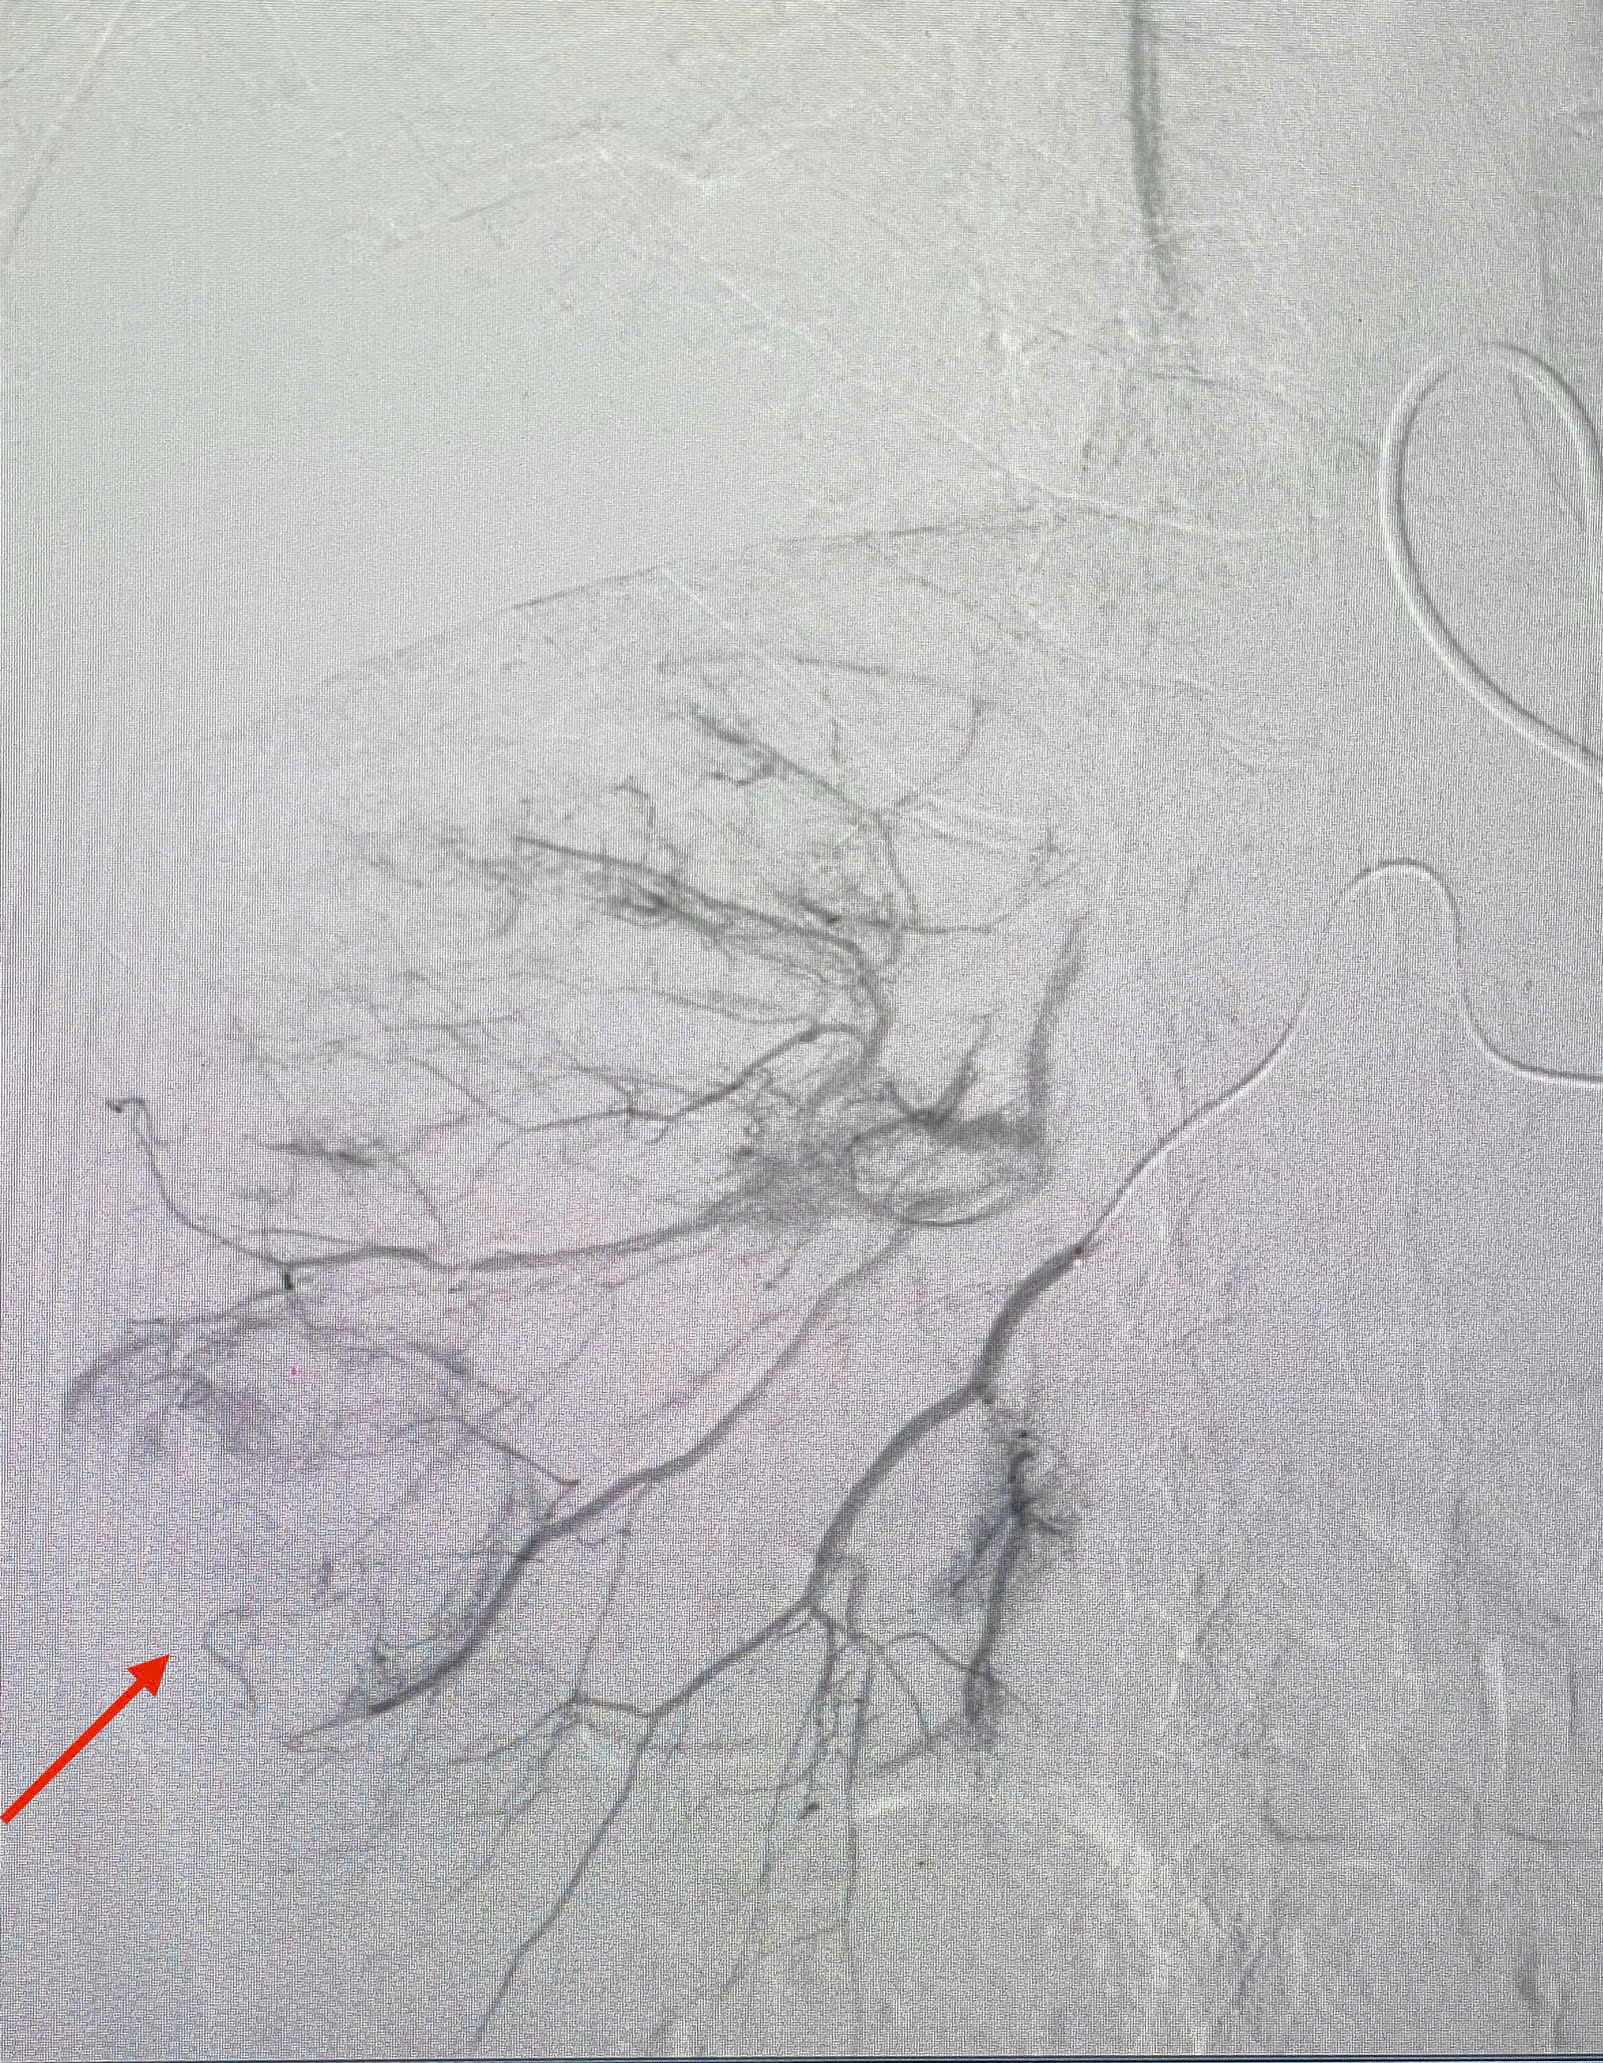

Dưới hướng dẫn của hệ thống máy chụp DSA tiên tiến, hiện đại, giúp bác sĩ tiếp cận và sử dụng các vật liệu thuyên tắc mạch ngắt nguồn nuôi khối u.

Hình ảnh: nút mạch u gan tại bệnh viện